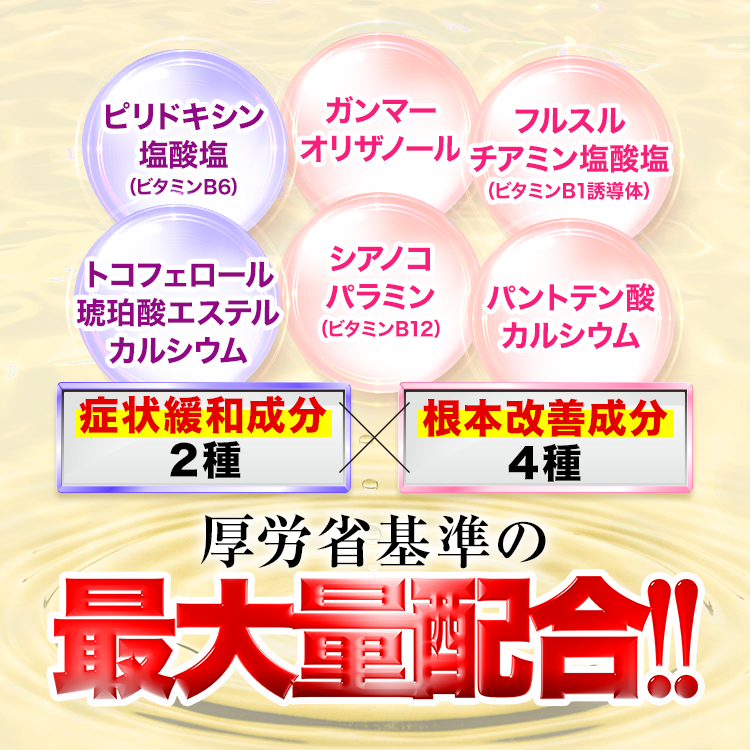

まずはじめにひとことで説明すると、

「ラクーダEXα」とは…

・症状を緩和する成分

・根本原因を改善する成分

が厚労省基準の最大量配合された薬です。

しびれや痛みを緩和するだけでなく、

飲み続けることで、

坐骨神経痛の根本原因を改善できるんです!

気になる人のために

その6つの成分について詳しく説明します。

しびれや痛みを緩和する成分がこの2つ。

※効果には個人差があります

これらの成分が

痛み止めと同じような効果を発揮し、

今ある症状をスーッとやわらげてくれます!

まずは1つ目の根本改善成分↓

そして最後に

神経の修復に関わる3つの成分↓

しかも、6成分すべてが

厚労省基準の最大量配合されているので

間違いなし!